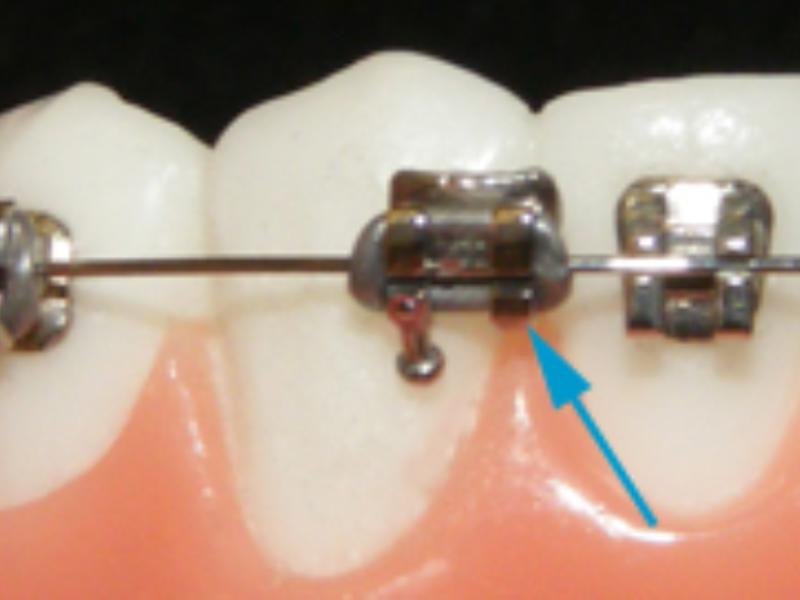

Ortodonti dişlerdeki konum bozukluğunu, çapraşıklığı, ayrıklığı düzelten bir tedavidir. Ortodontik tedaviden sonra dişlerinizde belirgin bir fark olacaktır. Ama düzelen dişleri bozulmadan tutmakta en az ortodonti tedavisi kadar önemlidir. Çünkü ortodonti tedavisi zor bir süreçtir, vakit ayırmanız gerekir, zaman zaman dişlerinizde ağrılar oluşur ve maliyettir. Bu kadar zahmetin altına girip dişlerinizi düzelttirdikten sonra tekrar bozulması canınızı çok sıkacaktır. Ortodonti tedavisinden sonra di